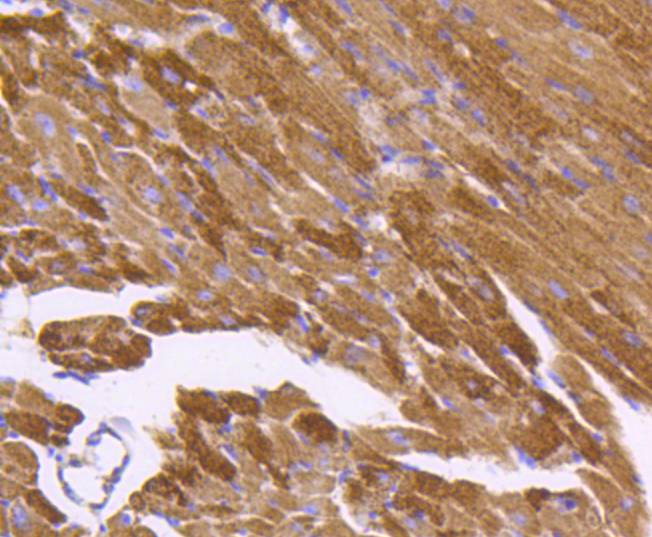

文献和实验:使用 Anti-phospho-Akt (Ser473) Rabbit mAb 对石蜡包埋的人乳腺癌组织进行免疫组织化学分析。(图 A)使用免疫组化试剂盒M&R HRP/DAB Detection IHC Kit,抗体 1:100 稀释;(图 B) 采用普通免疫组化试剂盒,抗体 1:25 稀释。 图 6 免疫组化实验检测 Erk1/2 表达 注:使用 Anti-Erk1/2 Mouse mAb与p44/42 MAPK (Erk1/2)Rabbit mAb 对正常小鼠心脏组织进行免疫